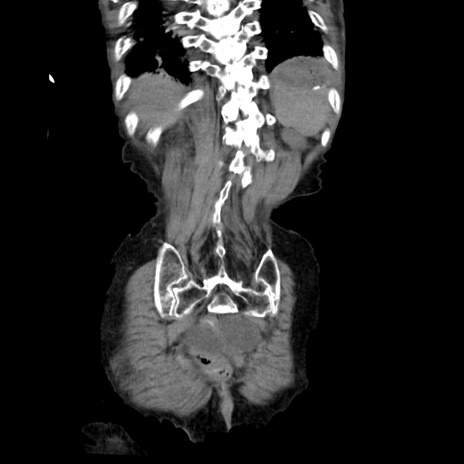

症例27(冠状断像)

【症例】80歳代女性

【主訴】嘔吐、腹痛

【現病歴】数時間前より嘔吐あり。心窩部痛出現し、徐々に右下腹痛あり。その後も数回嘔吐あり救急搬送となる。

【既往歴】左大腿骨頚部骨折手術

【身体所見】腹部は膨隆しているが軟らかく圧痛なし。腸雑音はやや亢進。

【データ】WBC 12000、CRP 19.05